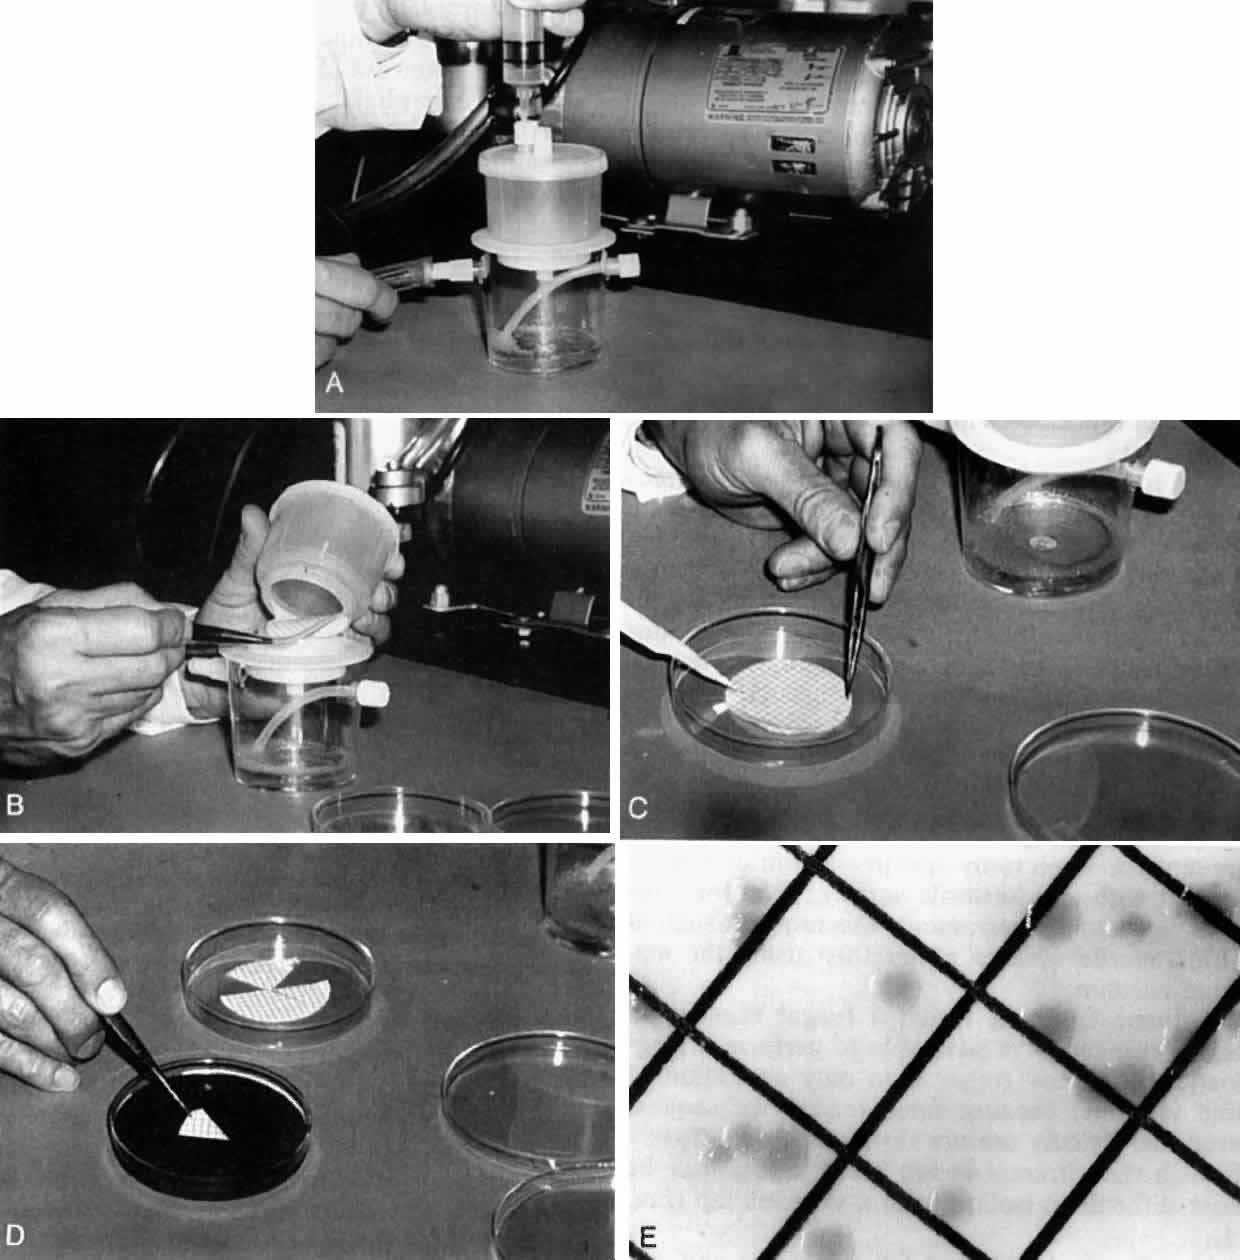

collagen remote from the site of cellular infiltration.  Fig. 21. Advancing edge of a granulomatous reaction. Scleral fibers are split and

separated by edema and then disrupted when invaded by the granuloma Fig. 21. Advancing edge of a granulomatous reaction. Scleral fibers are split and

separated by edema and then disrupted when invaded by the granuloma

|

Fig. 22. Electron micrograph of an area of active scleritis showing the plasma cell

infiltrate suggestive of an immune response. Note aggregated plasma

cells, with the characteristic whorled rough endoplasmic reticulum, in

the process of degeneration, releasing organelles and nuclear debris

into the extracellular matrix. (Uranyl acetate and lead citrate. X3000) (Courtesy of Dr. R. Tripathi) Fig. 22. Electron micrograph of an area of active scleritis showing the plasma cell

infiltrate suggestive of an immune response. Note aggregated plasma

cells, with the characteristic whorled rough endoplasmic reticulum, in

the process of degeneration, releasing organelles and nuclear debris

into the extracellular matrix. (Uranyl acetate and lead citrate. X3000) (Courtesy of Dr. R. Tripathi)

|

Fig. 23. Electron micrographs of scleral stroma at the periphery of an area of ulceration

in a patient with necrotizing scleritis. The left shows an active

fibroblastic cell, and the right shows collagen fibrils within intracellular

vacuoles (V) in the fibroblastic cell. (Left X15,375; right

X15,375) (Watson PG, Young RD: Changes at the periphery of a lesion necrotizing

scleritis: Anterior segment fluorescein angiography correlated with electron

microscopy. Br J Ophthalmol 68:781–789, 1984) Fig. 23. Electron micrographs of scleral stroma at the periphery of an area of ulceration

in a patient with necrotizing scleritis. The left shows an active

fibroblastic cell, and the right shows collagen fibrils within intracellular

vacuoles (V) in the fibroblastic cell. (Left X15,375; right

X15,375) (Watson PG, Young RD: Changes at the periphery of a lesion necrotizing

scleritis: Anterior segment fluorescein angiography correlated with electron

microscopy. Br J Ophthalmol 68:781–789, 1984)

|

Fig. 24. Electron micrograph of scleral stroma at the periphery of an ulcer in necrotizing

scleritis (same patient as in Figure 23) showing swelling and unraveling of collagen fibrils (arrows) in longitudinal

section (X29,270) and in transverse section (inset, X44,000). Fibrils

of all diameters are affected. (Watson PG, Young RD: Changes at the periphery of a lesion necrotizing

scleritis: Anterior segment fluorescein angiography correlated with electron

microscopy. Br J Ophthalmol 69:656–663, 1985) Fig. 24. Electron micrograph of scleral stroma at the periphery of an ulcer in necrotizing

scleritis (same patient as in Figure 23) showing swelling and unraveling of collagen fibrils (arrows) in longitudinal

section (X29,270) and in transverse section (inset, X44,000). Fibrils

of all diameters are affected. (Watson PG, Young RD: Changes at the periphery of a lesion necrotizing

scleritis: Anterior segment fluorescein angiography correlated with electron

microscopy. Br J Ophthalmol 69:656–663, 1985)

|

Fig. 25. Intense lymphocytic reaction and infiltration around a medium-sized arteriole

and nerve. Fig. 25. Intense lymphocytic reaction and infiltration around a medium-sized arteriole

and nerve.

|